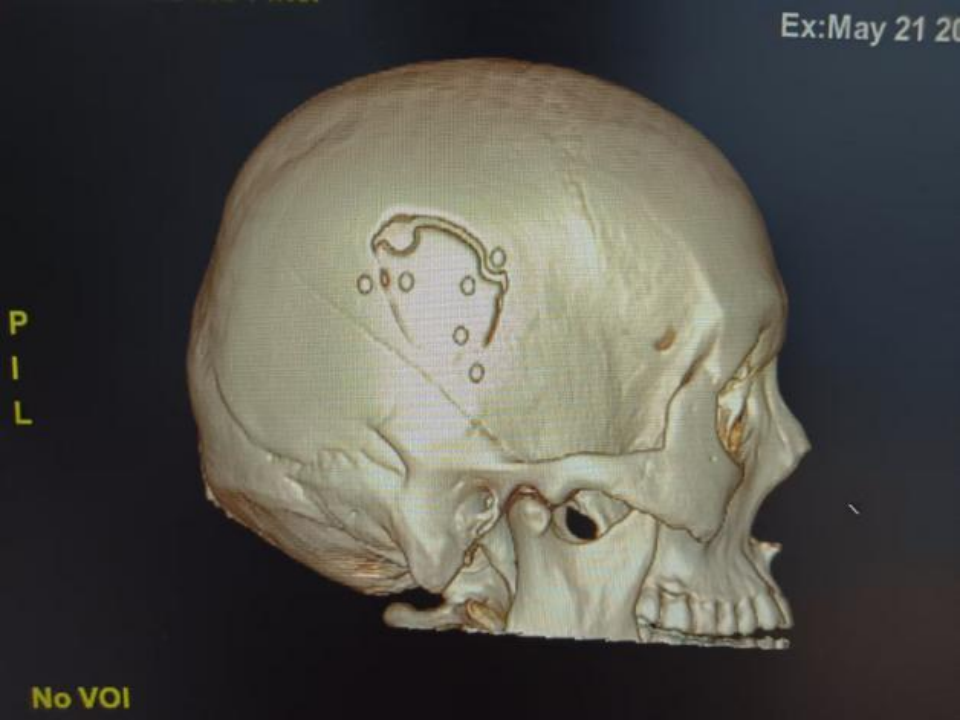

△术后颅脑CT三维重建

传统的手术方法是“问号形”或“马蹄形”切口切开头皮,根据血肿范围切除相当的骨瓣清除血肿,创伤大,切口一般在20cm左右,出血多,恢复慢。北京大学人民医院青岛医院采取神经内镜下清除硬脑外血肿,小切口,小骨窗,术中出血少,病人恢复快。